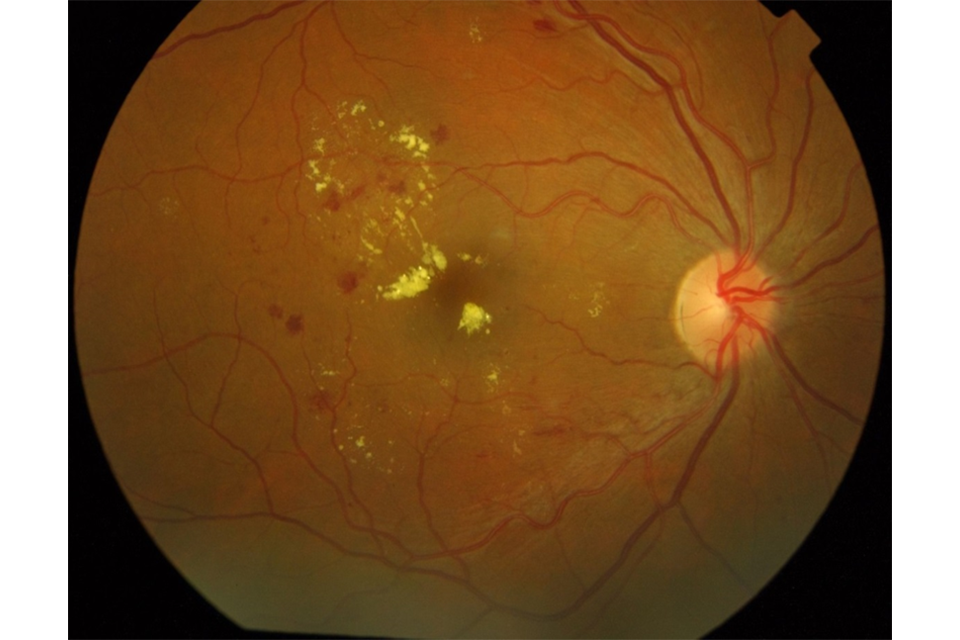

1. High risk maculopathy

High risk maculopathy is defined as macular exudation (circinate) greater than 1/2 disc area, within 1 disc diameter (DD) of the fovea and a drop in visual acuity in this eye to less than or equal to 6/12.

OCT image of retina showing high risk maculopathy